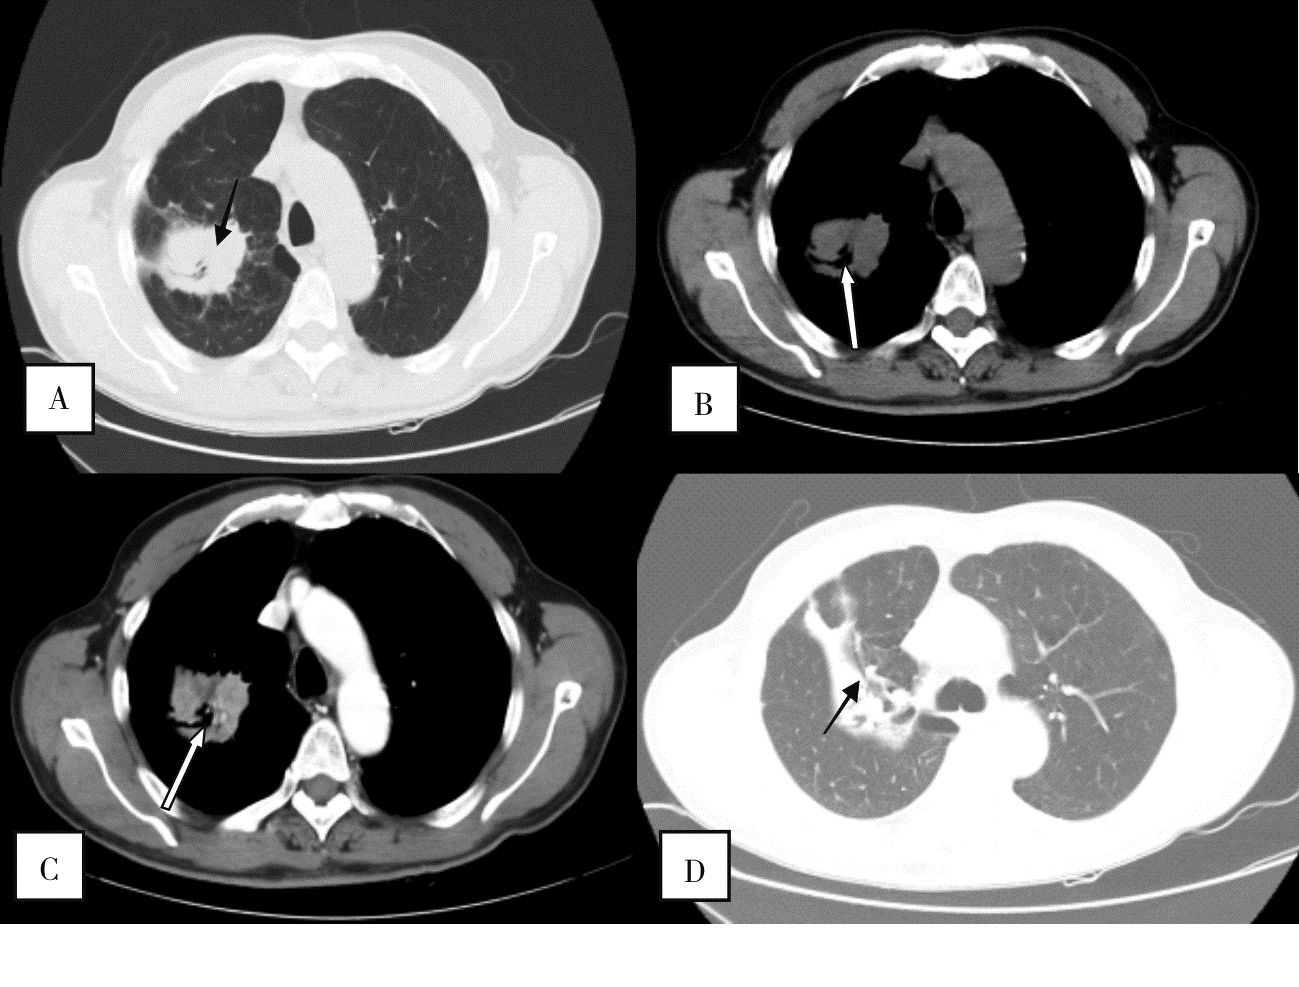

目的:探讨SMARCA4 缺失型非小细胞肺癌(SMARCA4-deficient non-small cell lung cancer, SMARCA4-dNSCLC)的临床与CT影像特征。方法:回顾性收集我院2018年1月至2022年1月期间经组织病理学证实的SMARCA4-dNSCLC患者,以同期收治SMARCA4表达完整的非小细胞肺癌(SMARCA4-intact non-small cell lung cancer, SMARCA4-iNSCLC)患者作为对照组。观察并记录SMARCA4-dNSCLC的临床资料与CT表现,并与SMARCA4-iNSCLC组比较。结果:共纳入SMARCA4-dNSCLC组42例,SMARCA4-iNSCLC组43例。SMARCA4-dNSCLC组男性、吸烟者及患慢性阻塞性肺疾病者比例更高。SMARCA4-dNSCLC组较SMARCA4-iNSCLC组更易出现上腔静脉综合征,而SMARCA4-idNSCLC组更常见咯血。CT表现上,SMARCA4-dNSCLC组肿瘤密度相对更均匀,囊变、坏死及钙化更少见,边界更模糊,且伴发阻塞性肺炎/肺不张比例较低。结论:SMARCA4-dNSCLC多见于老年男性,重度吸烟者,常伴有慢性阻塞性肺疾病。病灶好发于两肺上叶。CT多表现为密度相对均匀的软组织占位,边界不清,无囊变或坏死,罕见钙化。增强后不均匀强化。纵隔淋巴结转移常见。具备上述临床与CT特征者应警惕这一独特亚型的可能。

2组患者的CT特征比较[$\bar{x} \pm s$/n(%)]

| CT特征 | SMARCA4-dNSCLC组(n=42) | SMARCA4-iNSCLC组(n=43) | t/χ2 | P |

|---|---|---|---|---|

| 肿瘤位置 | 3.54 | 0.470 | ||

| 左肺上叶 | 14(33.33) | 12(27.91) | ||

| 左肺下叶 | 6(14.29) | 7(16.28) | ||

| 右肺上叶 | 17(40.48) | 15(34.88) | ||

| 右肺中叶 | 0(0) | 3(6.98) | ||

| 右肺下叶 | 5(11.90) | 6(13.95) | ||

| 肿瘤大小(mm) | 44.0±21.2 | 44.0±22.6 | 0.064 | 0.950 |

| 肿瘤密度[n (%)] | ||||

| 不均匀 | 17(40.48) | 35(81.40) | 14.73 | <0.00 1 |

| 均匀 | 25(59.52) | 8(18.60) | 15.23 | <0.010 |

| 病灶边缘不清晰/毛糙[n (%)] | 42(100.00) | 39(90.70) | 4.03 | 0.045 |

| 病灶囊变/坏死[n (%)] | 0(0) | 7(16.28) | 6.57 | 0.010 |

| 病灶钙化[n (%)] | 2(4.76) | 9(20.93) | 4.73 | 0.030 |

| 强化均匀度[n (%)] | ||||

| 不均匀 | 30(93.75) | 38(88.37) | 0.12 | 0.730 |

| 均匀 | 2(6.25) | 5(11.63) | 1.58 | 0.208 |

| 包绕血管[n (%)] | 9(21.43) | 10(23.26) | 0.09 | 0.760 |

| 累及食管[n (%)] | 3(7.14) | 1(2.33) | 1.07 | 0.300 |

| COPD[n (%)] | 11(26.19) | 23(53.49) | 6.53 | 0.010 |

| 肺不张[n (%)] | 10(23.81) | 19(44.19) | 4.73 | 0.030 |

| 纵隔淋巴结转移[n (%)] | 27(64.29) | 23(53.49) | 1.17 | 0.280 |

| 胸腔积液[n (%)] | 13(30.95) | 14(32.56) | 0.03 | 0.860 |